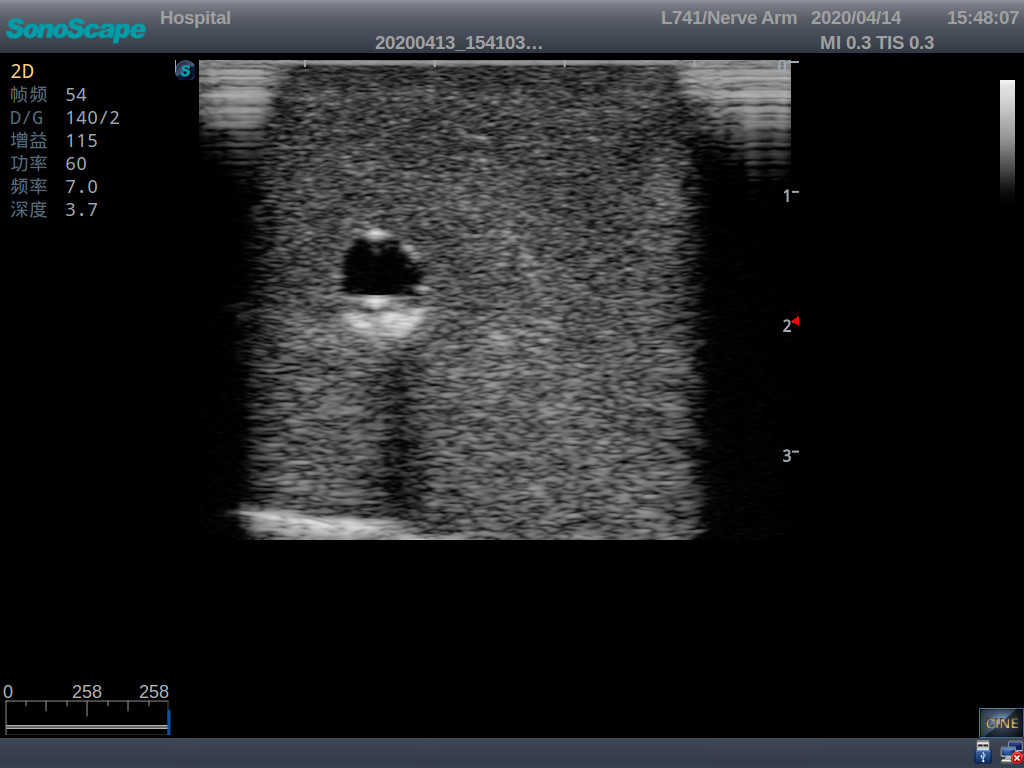

PICC Ultrasound Training Model

Model TYE1510.1

It is a model covering up from lobulus auriculae plane to the umbilical plane, and it has anatomical structures like clavicle, rib, sternocleidomastoid, jugular vein and basilic vein.

1)   Made of high molecular polymer ultrasound material, close to the real skin

2)   It can be used by real ultrasound machines

3)   Clear and real images of the tissues and organs (basilic vein and superior vena cava)

4)   When conducting vascular puncture, the piercing can be truly felt, and venous blood outflow can be seen

5)   Observe the guide wire marches